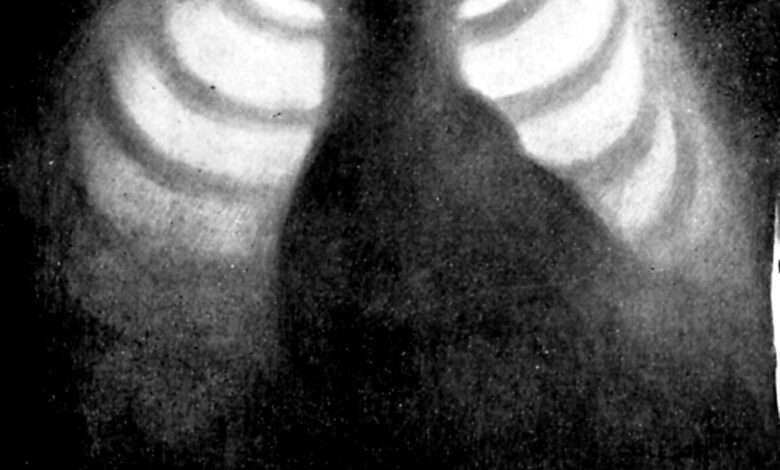

شرکت Oxipit با انتشار بیانیهای اعلام کرد ابزار هوش مصنوعی آنها که بدون کمک رادیولوژیست میتواند عکسهای اشعه ایکس قفسه سینه را بررسی اولیه کند، مجوز قانونی اتحادیه اروپا را دریافت کرده است.

با توجه به اینکه رادیولوژیستها در چند سال گذشته برای خودکارسازی کامل بخشهایی از کار خود تلاش داشتهاند و این ابزار که ChestLink نام دارد اولین هوش مصنوعی کاملا مستقل حوزه تصویربرداری پزشکی محسوب میشود، میتوان از آن به عنوان یک فناوری بسیار مهم و البته چالش برانگیز یاد کرد.

نحوه کار این ابزار نیز بسیار جالب است و پس از اسکن عکسهای اشعه ایکس قفسه سینه، گزارش بیماران سالم را به خود آنها و گزارش مواردی با یک مشکل احتمالی را برای رادیولوژیستها ارسال میکند تا توسط آنها نیز بررسی شوند.